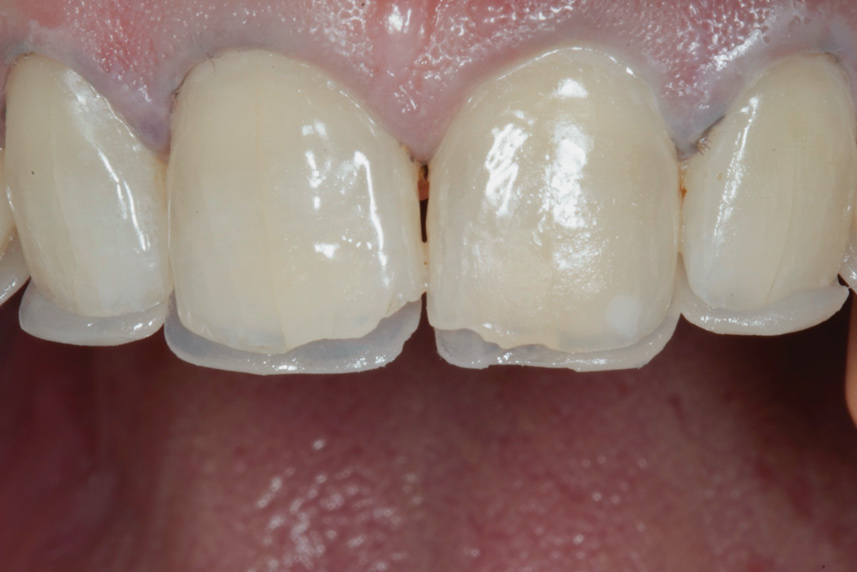

(12.) Postoperative upper anterior view.

Figure 12

During subsequent appointments, teeth Nos. 4 through 13 were restored with direct composite veneers in stages. Teeth Nos. 6 through 12 were treated first, followed by teeth Nos. 4, 5, and 13, respectively. Lingual and facial silicone putty indices were fabricated from the wax-up (Figure 7), and the lingual matrix was marked with a sharp probe at the existing incisal edge. Next, low-pressure air abrasion was used to clean the area and roughen the enamel to be bonded. Teeth Nos. 4 and 12 were isolated using polytetrafluoroethylene plumber's tape, and a 37.5 % phosphoric acid etching gel was applied and rinsed off. A layer of a fifth-generation bonding agent was applied and air-thinned, then a second layer was applied, air-thinned, and cured. The application of two layers has been shown to produce an increase in microtensile bond strength.20 After placement of the bonding agent, a clear enamel shade of microhybrid composite was applied into the lingual matrix in a thin layer and drawn slightly over the previously marked line. The composite was thickened toward the facioincisal line angle, which creates a natural "halo effect." The matrix was then adapted to the teeth, and the lingual shelf was briefly cured (Figure 8).

Any excess composite on the lingual surface of the teeth was removed before the lingual shelf was fully cured. Next, a microhybrid composite in a dentin shade was layered onto the teeth and the lingual shelf, drawn out into mamelon shapes with the aid of a sable brush, and fully cured. Using a hybrid composite for the lingual shelf and dentin layer provides wear resistance and strength for the restoration.21,22 Next, a small amount of material in a translucent blue shade was used in between and around the previously created mamelons in order to "lock in" the natural translucency and create a lower value appearance between the dentinal lobes (Figure 9). Finally, a layer of microfill in shade B1 was applied to full contour and cured. A matrix pull-through technique was used in the interproximal areas. Final curing was performed after the application of a glycerin gel to ensure a fully cured restoration surface. The decision to use a microfill in the visible areas that would not be placed under occlusal load was based on its superior polishability.22 A similar incremental layering technique was used on the cuspids and bicuspids.

With the patient sitting up, the incisal edges were finished parallel to the interpupillary line. After placing the patient back into a supine position, refinement of the primary anatomy was carried out with a fine grit, flame-shaped diamond bur. Coarse discs were then used to shape the cervical, middle, and incisal facial contours and open the incisal embrasures. The facioincisal line angles were marked with a pencil to ensure that proper placement was maintained during the shaping and finishing procedure. The proximal line angles, which were also marked with a pencil, were finished using medium coarse discs to establish light reflecting and light deflecting areas.

Once the primary anatomy was finished, secondary anatomy was created by first marking off the desired position of developmental grooves with pencil and then placing them carefully with a flame-shaped diamond bur and abrasive points. The patient was also fitted with a bleaching tray for the lower arch and instructed to bleach only the lower anterior teeth.

The final polish was performed using a series of fine grit discs in various sizes, and a glass-like luster was achieved by applying aluminum oxide polishing paste with felt discs and points under light pressure.